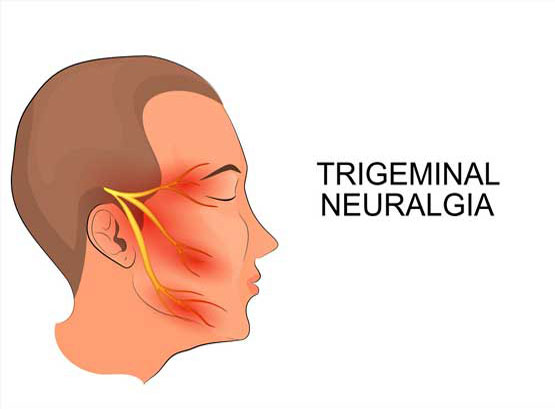

Brief profile: Dr Arghya Mukherjee, a university certified doctor for pain management with background knowledge of Anaesthesiology has been providing treatments for those affected with acute and chronic pain. Dr Arghya Mukherjee applies his expertise in a wide variety of advanced, minimally invasive procedures as part of a comprehensive approach to treat patients with acute and chronic pain.

Fields of expertise: Dr Arghya Mukherjee has special interest in Ultrasound guided acute and chronic interventional pain management procedures. He performs Fluoroscopy guided interventional pain management procedures for chronic and cancer pain as well with expertise.